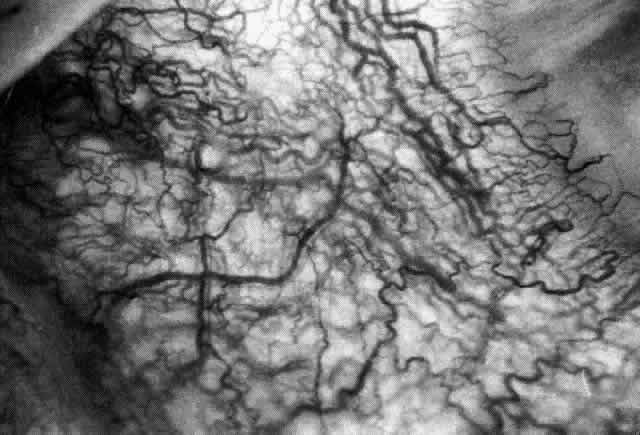

The redness of simple episcleritis may be intense, varying from a fiery-red or a brick-red discoloration to a mild red flush, but it does not have the bluish tinge that is seen in scleritis. The distribution is usually sectorial but can involve the whole anterior segment of the globe. The episcleral vessels are engorged but retain their normal radial position and architecture (Figs. 13 and 14; Color Plate 1A). In simple episcleritis, there is a diffuse edema of the episcleral tissues. These tissues are sometimes infiltrated with gray deposits that appear yellow in red-free light. Surprisingly, the eye is rarely tender to the touch.

Fig. 13. Infiltration of the episclera in which the superficial episcleral vessels show maximal congestion. Conjunctival vessels are slightly congested, as is the deep episcleral plexus, whose irregular criss-cross pattern can be seen deep to the radially arranged superficial episcleral plexus.

Fig. 14. Diffuse inflammation. Superficial vessels are maximally engorged and retain their radial pattern and architecture. (See Figures 27 and 34.) (Watson PG: Connective tissue disorders and the eye. In: Recent Advances in Ophthalmology, Vol 5, pp 214–277. London, Churchill-Livingstone, 1975)